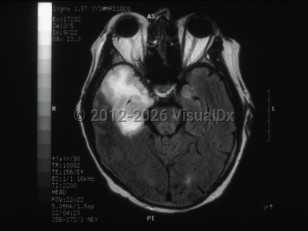

Herpes simplex virus encephalitisHerpes simplex virus encephalitis

Subdural empyemaSubdural empyema

Meningoencephalitis